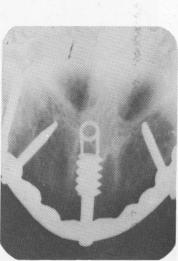

Fig. 4-64. This vent-plant broke 8 months after its insertion into the nasal septum.

4 Broken vent-plant implant eight months after insertion in nasal septum